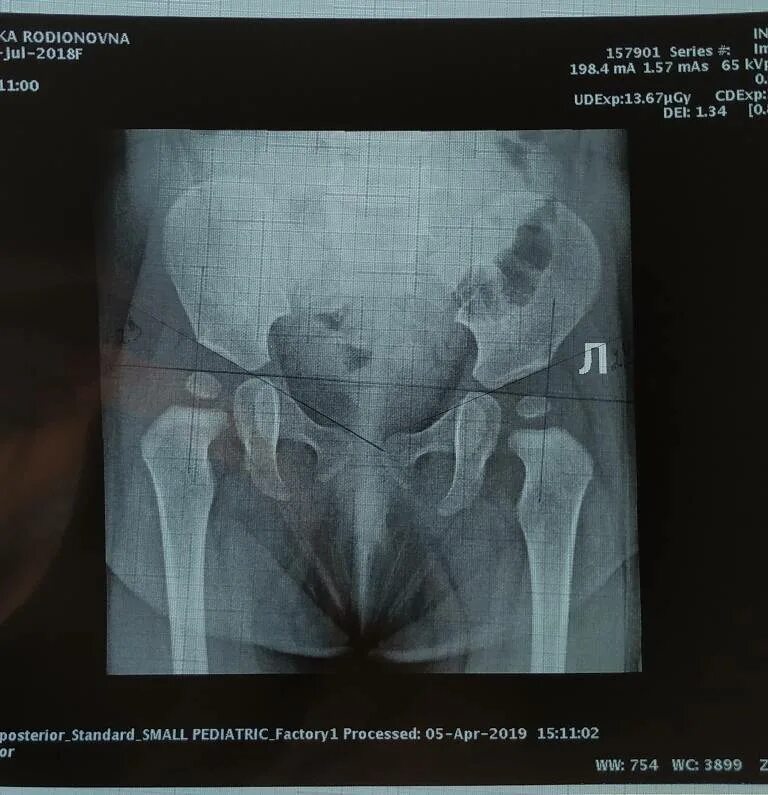

Как лечить дисплазию сустава у детей